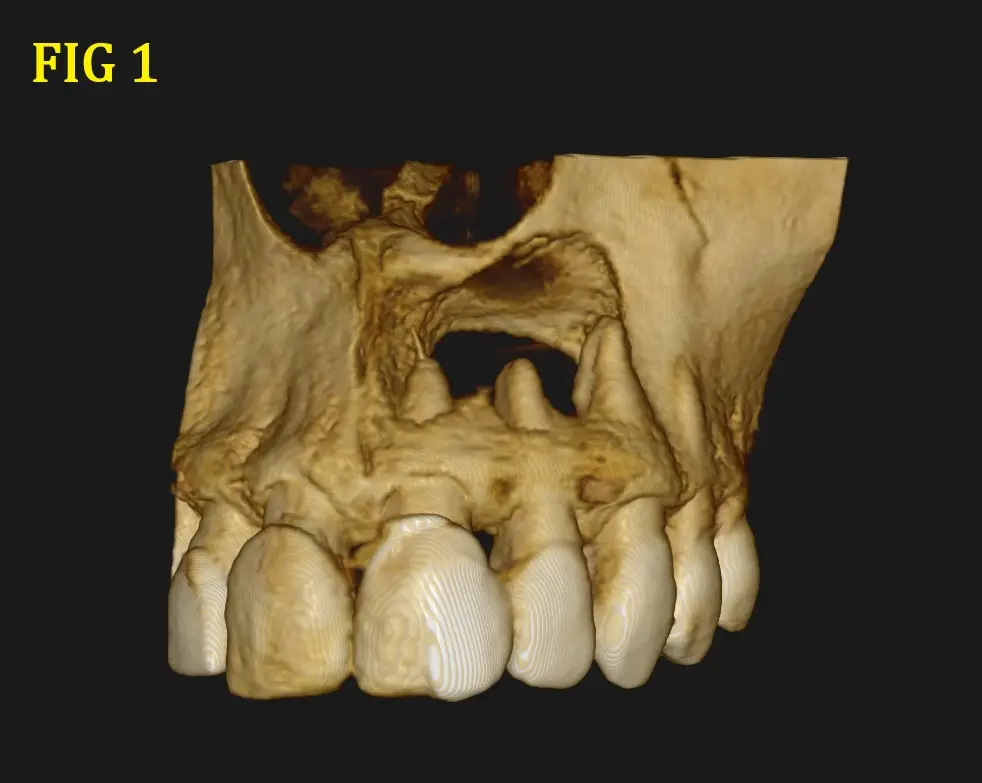

Al realizarle la tomografía se observó una imagen hipodensa (Fig. 1 y 2) proveniente de la pieza dental 21, pieza en la que fue realizada un tratamiento de conducto, donde se llega a observar una sobre obturación (Overfilling) (Fig. 3 y 4), el material hiperdenso se observa sobresalir del ápice radicular sobrepasando el limite CDC (conección Dentino-Cementaria) , generando el quiste periapical. ( Fig. 5). El quiste va generando presion a las piezas adyacentes y se extiende desde pieza dental 21 a 23 inclusive.

Se describe la tipica imagen expansiva sobre los tejidos scircundantes, tipo globo con agua, que tiene limites bien definidos, aunque por su tamaño y posibles reagudizaciones en algunas zonas se encuentra ausente o cueste distinguirlo, provocando ensanchamiento de las tablas libres y adelgazamiento